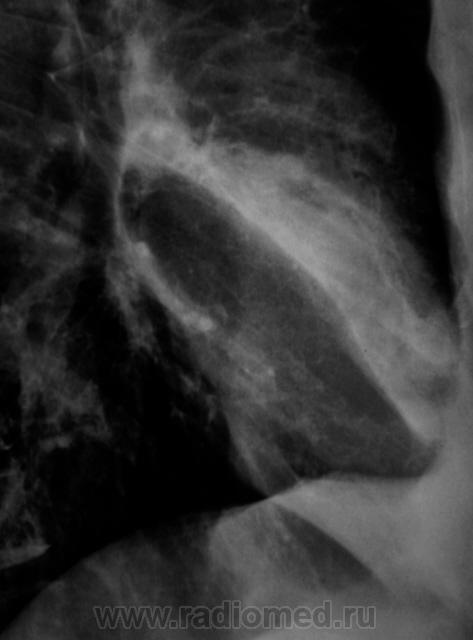

Контроль через 1 месяц после противовоспалительной терапии.